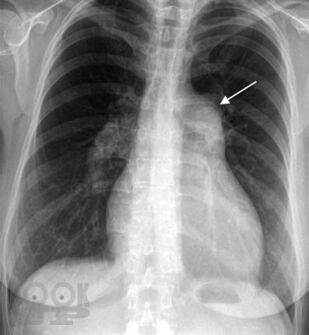

Аннотация

Монография посвящена проблемам диагностики и лечения легочной гипертензии. Термином «легочная гипертензия» объединяют группу нозологий с общим диагностическим критерием — повышением давления в легочной артерии. В работе представлены вопросы патогенеза и генетические основы легочной гипертензии, дана ее современная классификация, описаны формы легочной артериальной гипертензии, легочной гипертензии вследствие патологии левых отделов сердца, легких или хронической тромбоэмболии легочной артерии. Дан диагностический алгоритм, включающий оптимальные методы диагностики. Монография представляет современные возможности лечения легочной гипертензии, знакомит с данными ключевых рандомизированных клинических исследований и позволяет заглянуть в будущее. Работа создана специалистами ведущих экспертных центров нашей страны во главе с ФГБУ «Российский кардиологический научно-производственный комплекс» МЗ РФ и предназначена для кардиологов, пульмонологов, терапевтов, ревматологов, а также для практикующих врачей, имеющих отношение к обследованию и лечению больных с легочной гипертензией.